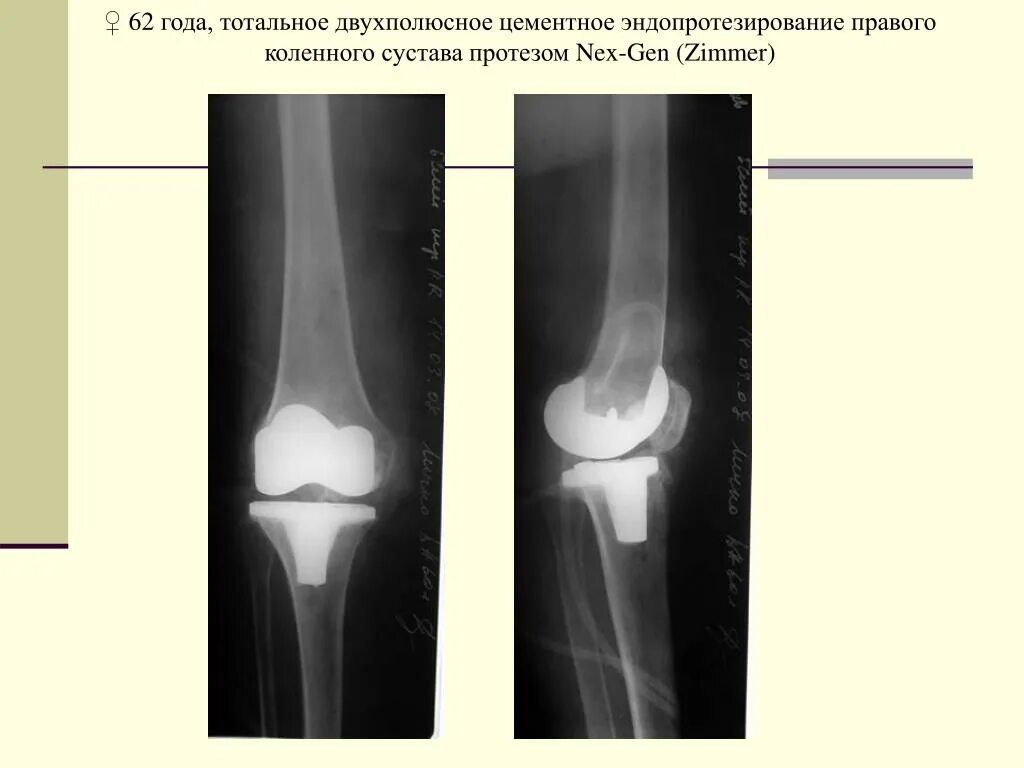

После тотального эндопротезирования коленного сустава